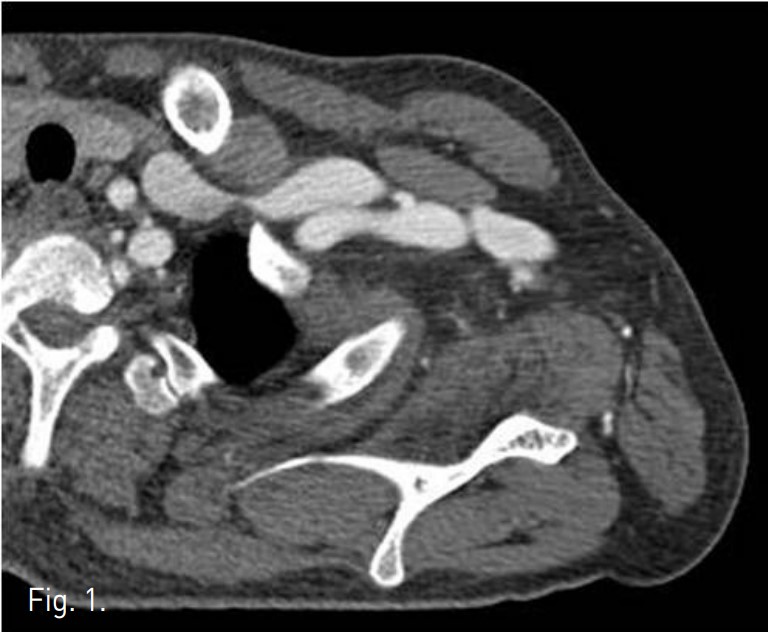

CT에서 left subclavian vein이 subclavius muscle과 anterior scalene muscle 사이에서 좁아져 있는 것이 관찰된다(Fig. 1). 팔을 내리고 시행한 venogram에서 subclavian vein이 막혀 있고 wire가 통과하지 않았으나(Fig. 2A), 팔을 머리 위로 올리고 시행한 venogram에서 subclavian vein의 distal portion이 관찰되고 catheter가 통과되었다(Fig. 2B).

Fig. 1.

Fig. 1. It shows extrinsic compression of left subclavian vein by subclavius muscle anteriorly and anterior scalene muscle posteriorly.